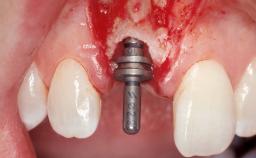

Immediate Flapless Placement of an Implant in a Maxillary Left Central Incisor Site

A 29-year-old female patient presented for treatment to replace the upper left central incisor tooth with an implant- supported restoration. The tooth had been intermittently symptomatic for the previous 12 months. The tooth had originally suffered trauma about 15 years previously. Several endodontic treatments had been performed, including an apicectomy procedure to retain the tooth. The patient was healthy and a non-smoker. She had reasonable expectations in regard to esthetic outcomes and the risk of marginal tissue recession following treatment. At medium smile, the gingival margins of the upper teeth were visible, with a display of 3 to 4 mm of the gingival margins. Gingival recession of tooth 21 and a discrepancy in the gingival levels between teeth 11 and 21 was observable during normal speech and smile.

Placement Protocol | Immediate implant placement |

Tooth Site | Maxillary incisor or canine |

Socket Morphology | Single-root socket |

Socket Integrity | Damage to one or more bone walls |